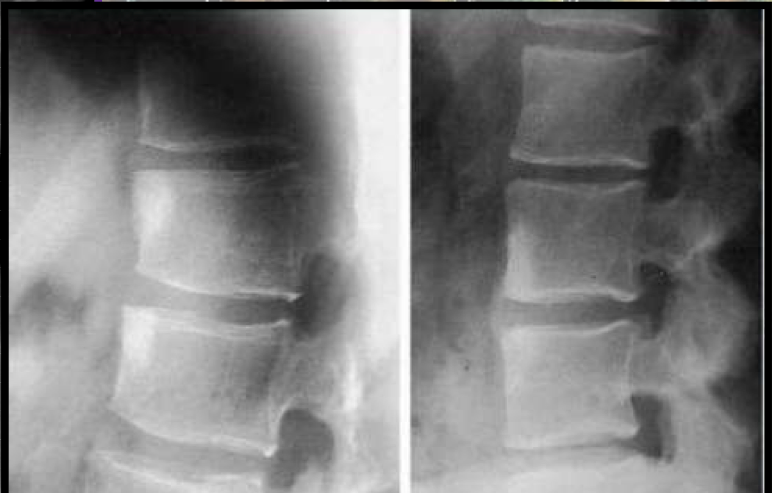

What two findings of AS are found in this image

Corner erosions (Romanus lesions)

Reactive sclerosis (shiny corner)

Loss of anterior concavity (vertebrae squaring)